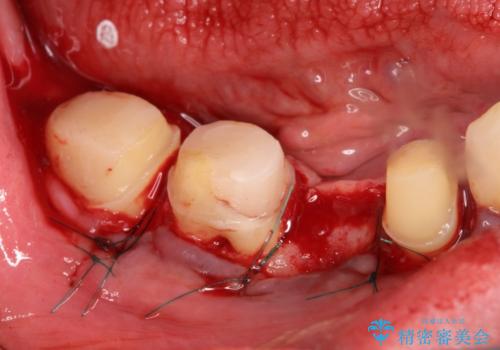

また、虫歯が歯肉の中まである場合はAPF(歯肉弁根尖側移動術)も行なっています。

- 外科手術のため、術後に出血、痛みや腫れ、違和感を伴います